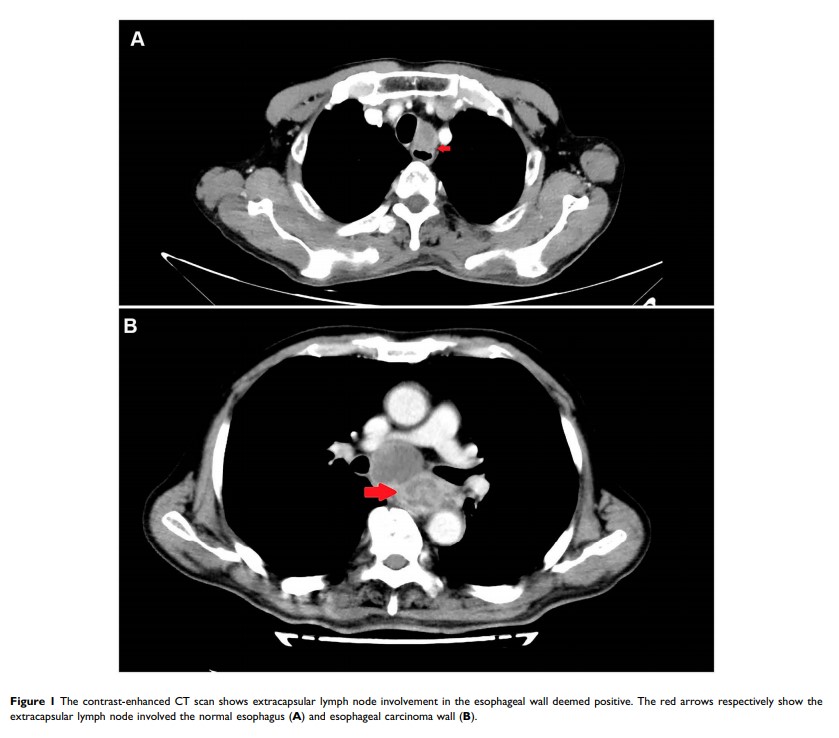

放疗期间和之后食管的囊外淋巴结对食管穿孔的影响:倾向得分匹配分析